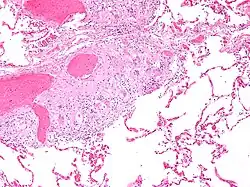

Micrografía de cuerpos de asteroides en sarcoidosis pulmonar. Tinción con hematoxilina eosina. -